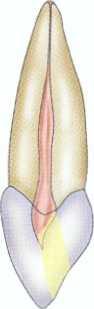

FIGURE 2-13 A, Removal of the amalgam permits inspection of the tooth for fractures. The use of microscopy allows identification of a mesiodistal fracture. The pulp chamber has not been entered. B, On entering the pulp chamber, the clinician notes a fracture across the pulpal floor from mesial to distal. Wedging a Glick instrument into the access allows the clinician to visualize the fracture spreading and closing in this hopeless tooth. Although this gross fracture was visible with loupes, the extent of many fractures cannot be seen. Diagnosis and prognostication then become guessing games at best. Note the white dot of the MB2 canal located (in vain) with a Mueller bur above the fracture about halfway between the fracture and the MB canal; this was not visible without the microscope.